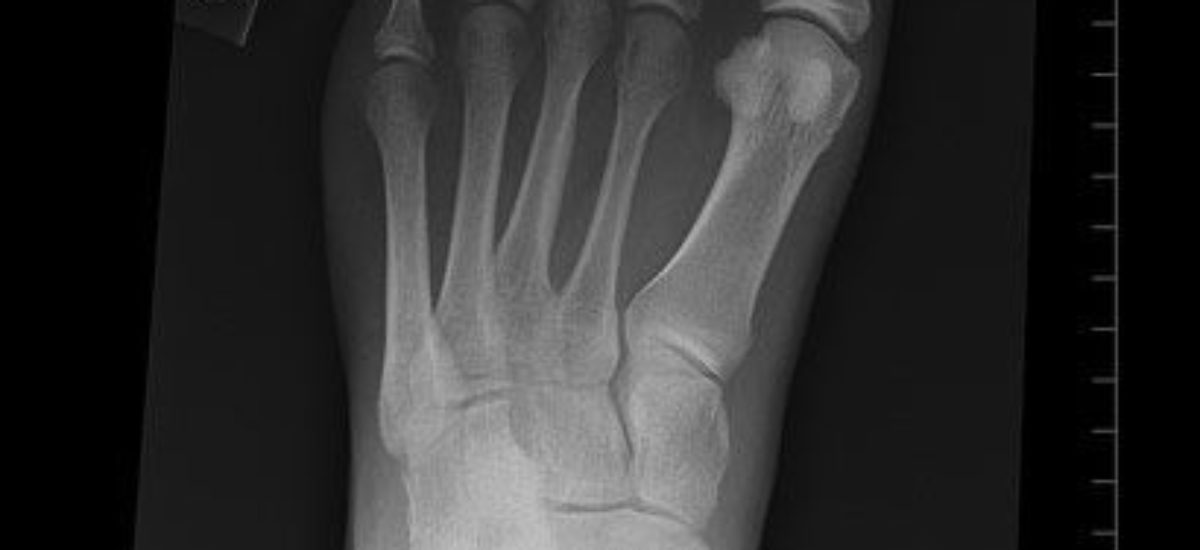

Al igual que la gota, esta afección implica la formación de cristales en las articulaciones pero con la diferencia de que los causantes de la inflamación articular se forman a partir de una sal de calcio: el dihidrato de pirofosfato cálcico. Su nombre se debe a que la clínica de la afección es similar a la de la gota y afecta a rodillas, pubis, muñecas y nudillos, sobre todo la articulación metacarpofalángica. Con el tiempo, los depósitos de esta sal en el interior del cartílago articular se calcifican.

Pocas veces esta afección provoca algún tipo de molestia, y suele encontrarse por casualidad en algún examen radiológico. Sin embargo, en aquellos casos que sí produce dolor persistente en la articulación éste no se debe a la calcificación sino a que se produce un particular tipo de artrosis. También puede provocar hinchazón con calor, rubor, lo que dificulta la movilización de la articulación.

Más del 90% de las personas afectadas desconocen que tiene condrocalcinosis, y pocos casos se deben a alguna alteración metabólica o endocrina. Su incidencia es más elevada en mayores de 50 años y en mujeres. La frecuencia de aparición aumenta con la edad: a los 65 años, un 5% de las personas la padecen; a los 80, la cifra alcanza un 30%. En los adultos de edad avanzada es una causa común de artritis aguda en una articulación. El diagnóstico se basa en un examen radiológico y mediante muestras de líquido sinovial.